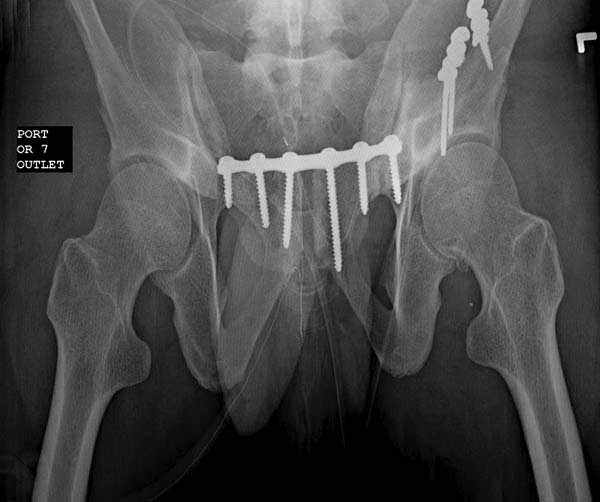

Реконструктивные пластины слабые, и для усиления необходимо установить дополнительную верхнюю пластину или оставить передний наружный фиксатор. Предпочтительным для фиксации считаю специальную для симфиза жесткую пластину из набора Joel Matta (Stryker), которая лучше, чем остальные, создает жесткость.

Здесь представлен случай 38 летнего больного (падение с высоты 9 метров) с нарушением тазового кольца. При поступлении для стабилизации передне-нижний аппарат наружной фиксации и на 6й день, вчера, операция из двух доступов.

Представлены снимки техники проведения стержней. Через место прикрепления прямой мышцы в Inferior Iliac Spine в направления вырезки создается жесткость. Weber clamp изнутри таза для репозиции, и фиксация после репозиции перелома крыла подвздошной кости. Наружный аппарат удален, нагрузка предполагается через два месяца.